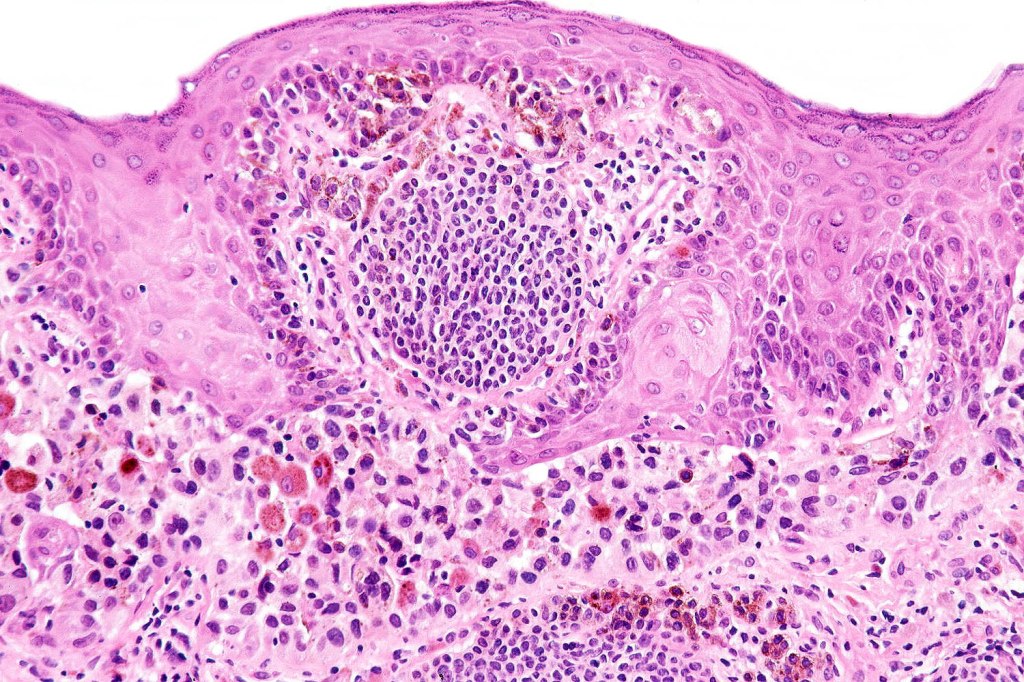

Histological features

•Junctional/compound

•Large dyscohesive nests with retraction artifact, not restricted to the tips of the epidermal ridges

•Bridging common, often over multiple rete ridges

•Variable atypia (can be marked)

•Central pagetoid spread

•Superficial dermal atypia